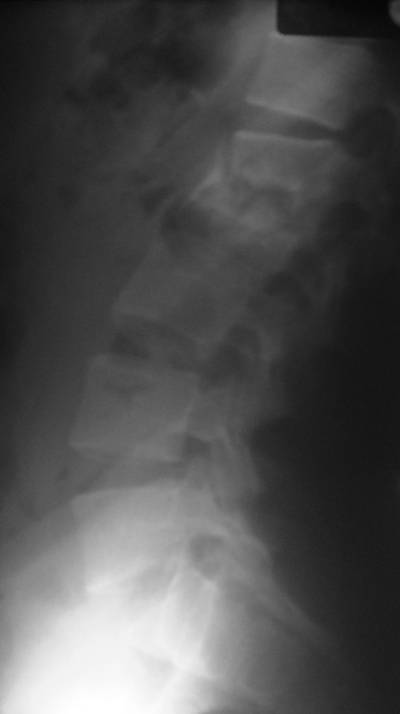

- Figura No 2a

- Figura No 2b

- Figura No 2c

- Figura No 2d

- Figura 2 Texto